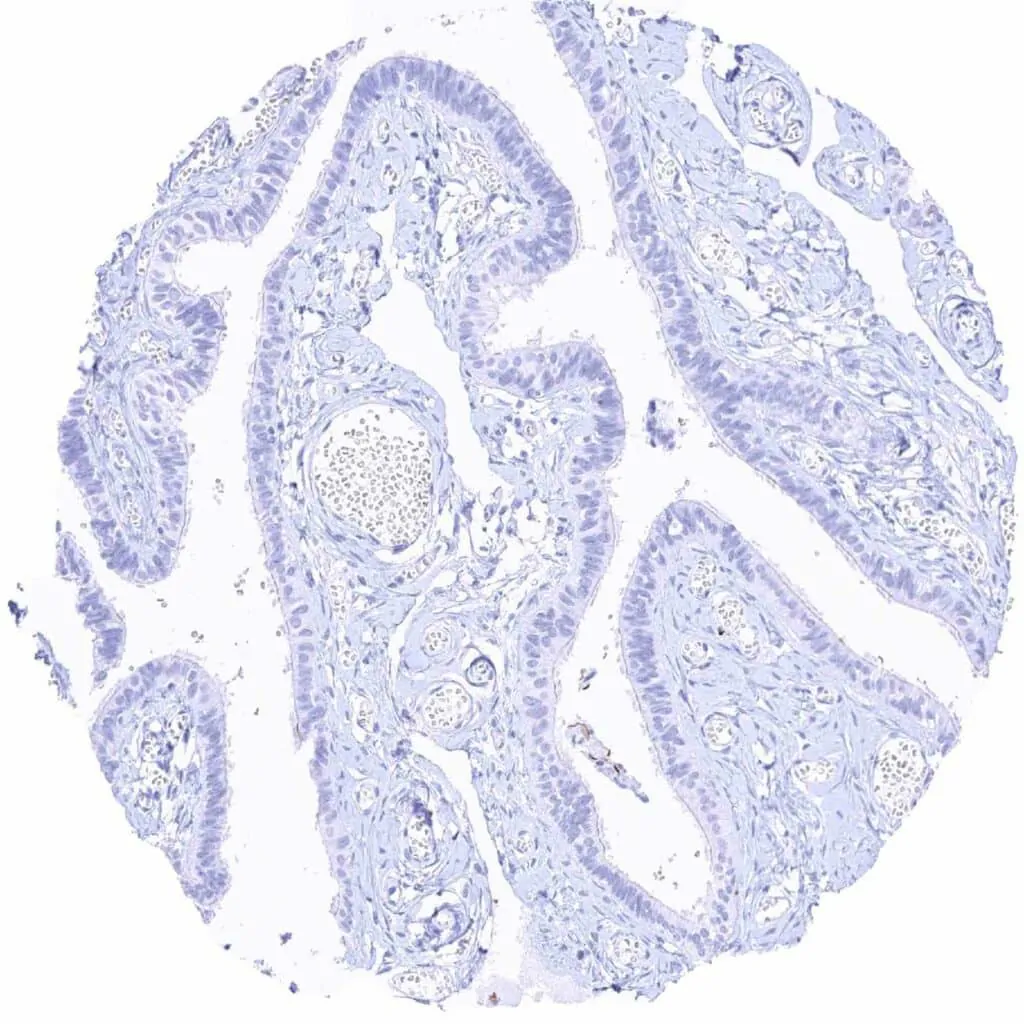

Fallopian tube, mucosa